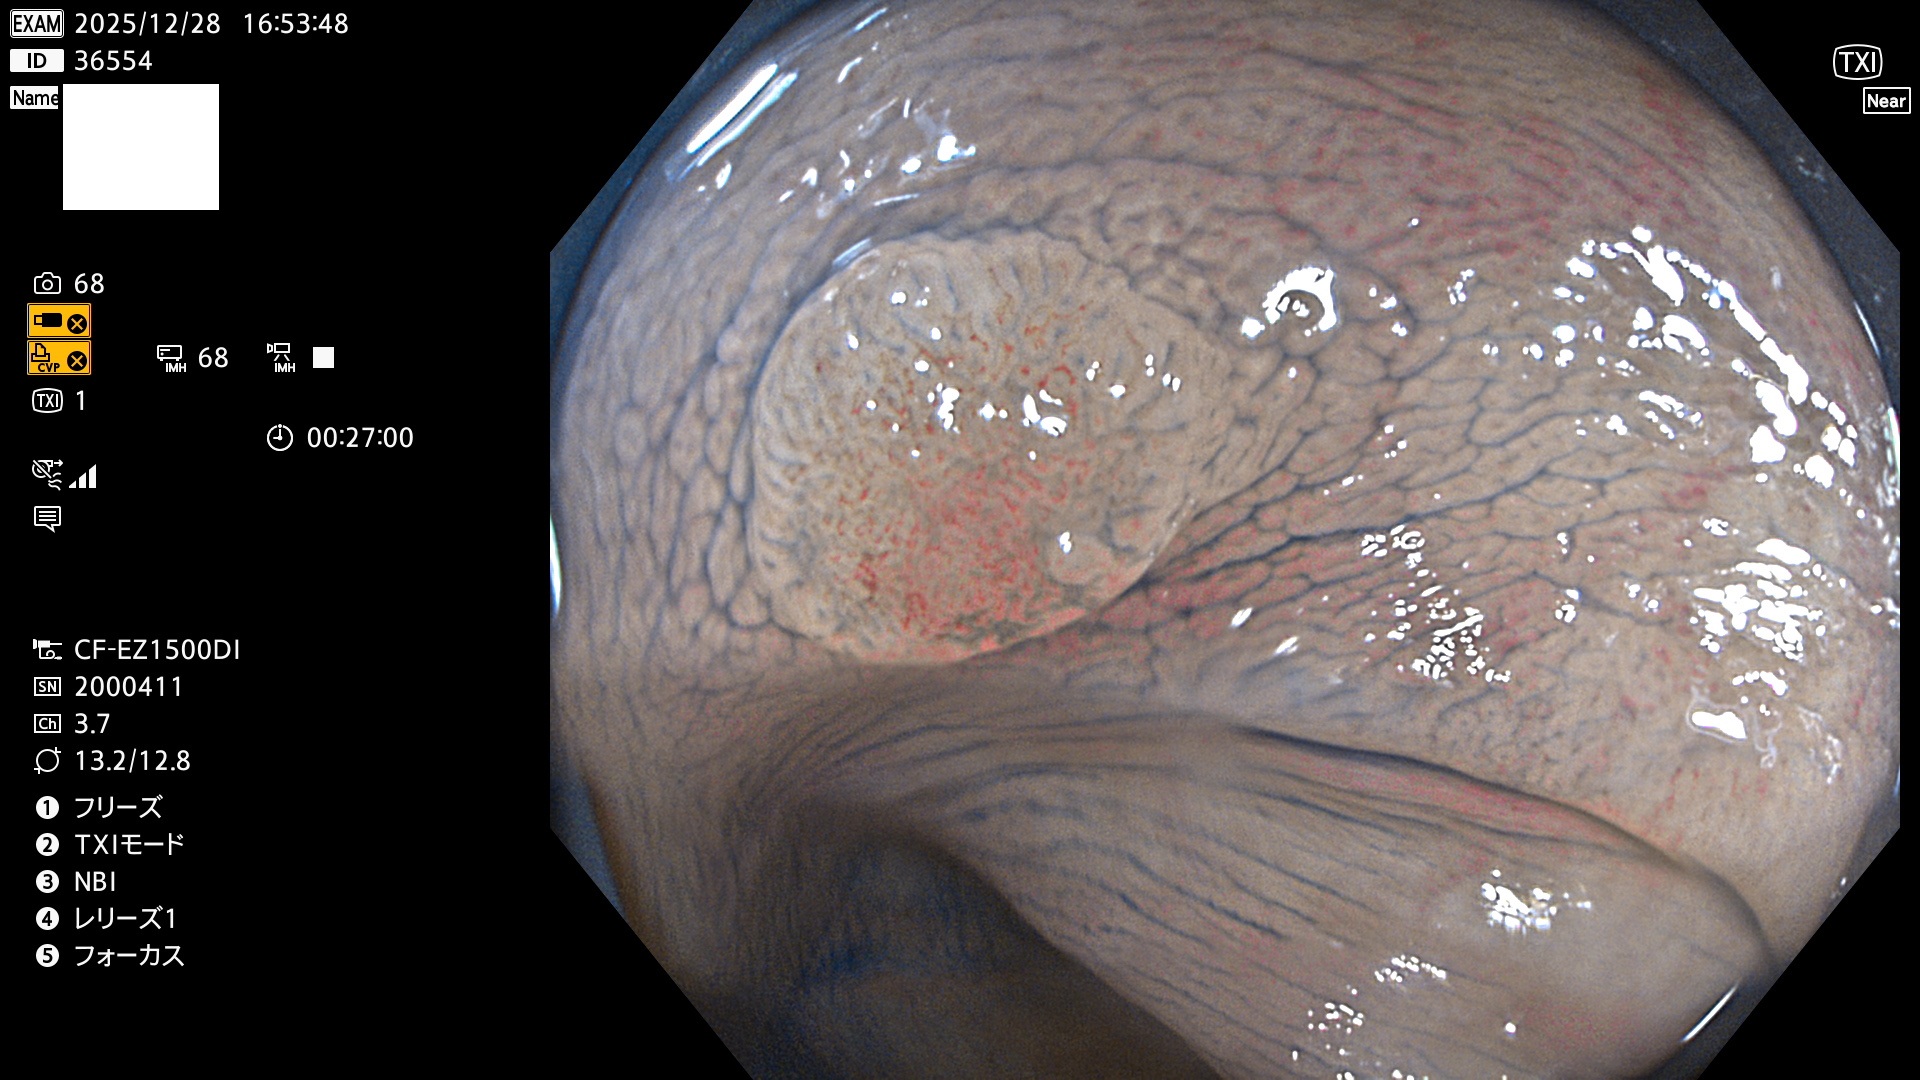

完全に平坦な物をUb、陥凹している物をUcと呼びます。Ubは認識が困難で、Ucはびらん(炎症)と紛らわしいために見落とされやすく、「内視鏡後・大腸癌」の原因になります。

専門的)Uc=De Novo癌? 内視鏡の解像度が低かった時代、このような説もありました。しかし今日の高精度内視鏡では良性の微小なUc型腺腫(APC遺伝子異常の腺腫)が日常的に見つかります。Ucこそが多段階発癌(Adenoma-Carcinoma Sequence)のMain Routeです。

毎週の検査(木・金・土・日)に発見されたUbとUc型・腺腫を、その週の日曜の夜にUPし1週間、提示します。

2025年12月18日〜12月29日の8日間(80件)13個 (Uc_ADR=13個/80人=16%)